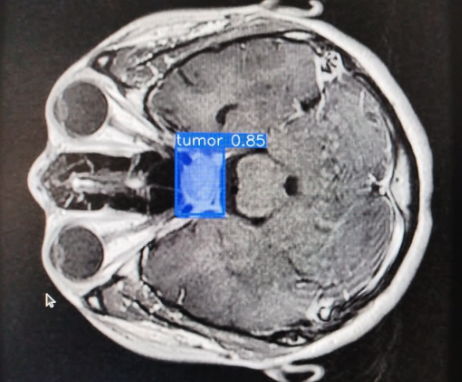

Detection of brain tumors using artificial intelligence based on convolutional neural networks (CNNs).